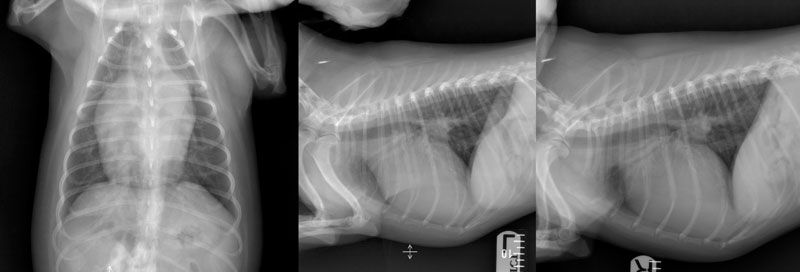

Figure 1: Preoperative dorsoventral (left), left lateral (middle), and right lateral (right) radiographs of the thorax of a 2.5-year-old female spayed Cavachon with a patent ductus arteriosus demonstrating moderate generalised cardiomegaly with focal bulging in the region of the proximal descending aorta, left atrium, and auricular appendix, and concurrent pulmonary vein congestion. There is also moderate divergence of the left and right mainstem bronchi (‘bow-legged cowboy’ sign) and moderate dorsal displacement of the thoracic trachea. Images courtesy of Dr Seamus Hoey (University College Dublin).

Thoracic radiographs: Radiographs may identify signs supportive of PDA but cannot be used as a sole method of diagnosis. Typical radiographic changes include moderate to severe left-sided cardiomegaly and possibly a triple knuckle/bulge sign (Figure 1). The latter is formed by enlargement of the aorta (located at 12-1 pm), pulmonary artery (1-2 pm), and left auricle (2-3 pm) on a well-positioned dorsoventral radiograph. However, in one study (Van Israël et al, 2002), the radiographic triad of dilation of these three structures was noted in only about a quarter of cases. Elevation of the trachea, pulmonary oedema, and overperfusion of the pulmonary vasculature may also be observed (Van Israël et al, 2002; Van Israël et al, 2003).